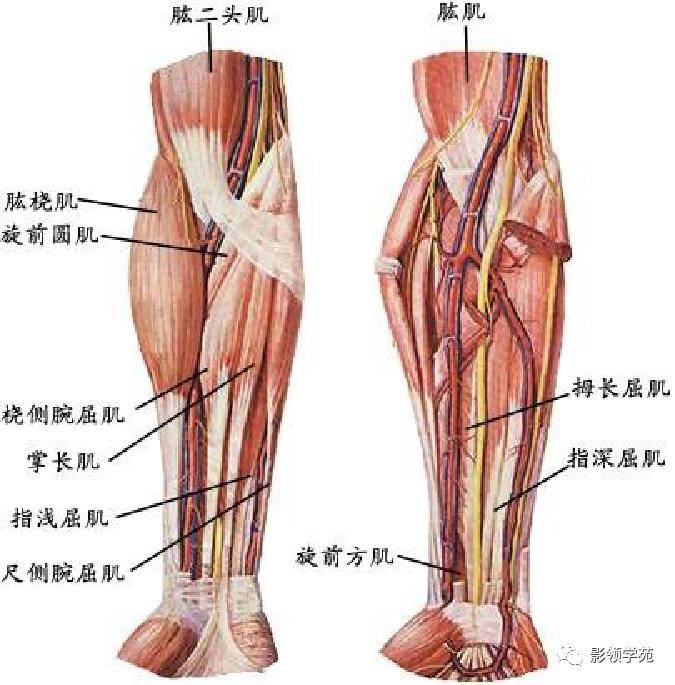

前臂动脉走向

前臂动脉走向